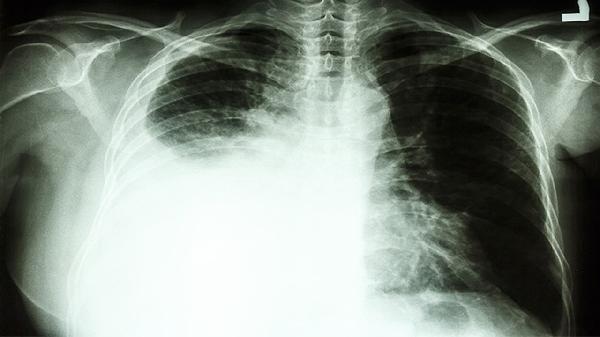

3、胸腔穿刺引流:

恶性胸腔积液压迫肺组织时,需行胸腔闭式引流术排出积液。每次放液不超过1000毫升,术后可胸腔注入博来霉素等硬化剂防止复发。操作需严格无菌,避免气胸、出血等并发症。